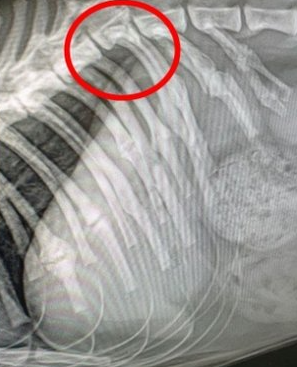

그는 고양이의 상태에 대해 “척추 골절로 하반신이 마비돼 현재 대소변을 가리지 못하고 있다” 며 “척추 골절뿐 아니라 이전 학대로 발생한 다발성 골절로 인해 갈비뼈 13개가 골절됐다” 고 밝혔다.